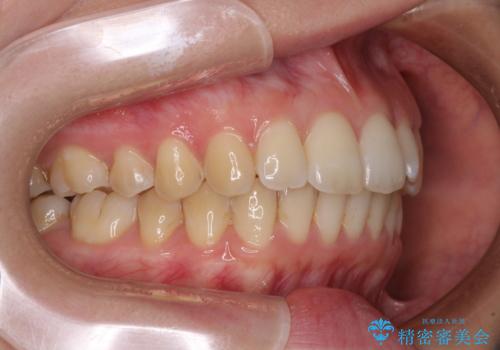

前歯のデコボコを解消 インビザラインによる矯正治療

- 上下前歯のデコボコと深い咬み合わせを気にして来院された患者様です。

インビザラインによる上下歯列の拡大と、IPR(歯と歯の間を削る)にるスペースの獲得により、前歯のデコボコを改善することとしました。

上の前歯をもう少し整えたかったのですが、患者様の治療を早く終了させたいという希望により、細かい叢生を残しての終了となりました。